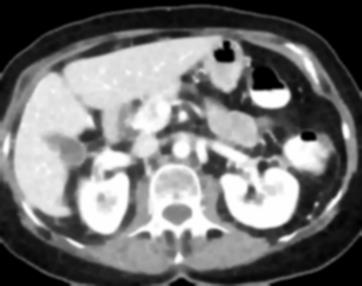

Due to the constraints of the imaging device and high cost in operation time, computer tomography (CT) scans are usually acquired with low intra-slice resolution. Improving the intra-slice resolution is beneficial to the disease diagnosis for both human experts and computer-aided systems. To this end, this paper builds a novel medical slice synthesis to increase the between-slice resolution. Considering that the ground-truth intermediate medical slices are always absent in clinical practice, we introduce the incremental cross-view mutual distillation strategy to accomplish this task in the self-supervised learning manner. Specifically, we model this problem from three different views: slice-wise interpolation from axial view and pixel-wise interpolation from coronal and sagittal views. Under this circumstance, the models learned from different views can distill valuable knowledge to guide the learning processes of each other. We can repeat this process to make the models synthesize intermediate slice data with increasing inter-slice resolution. To demonstrate the effectiveness of the proposed approach, we conduct comprehensive experiments on a large-scale CT dataset. Quantitative and qualitative comparison results show that our method outperforms state-of-the-art algorithms by clear margins.